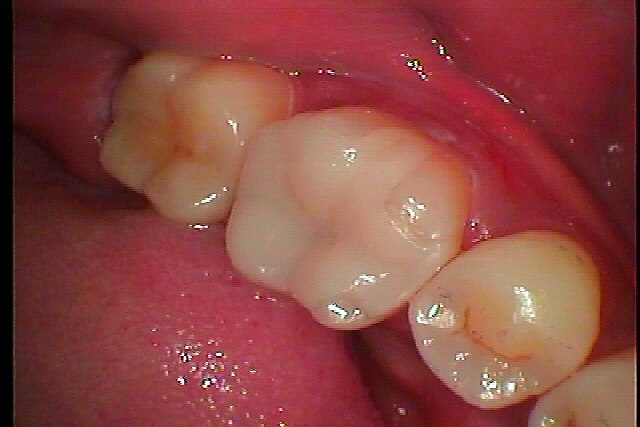

大臼歯部の虫歯の治療からのセラミック治療へ| |広島市安佐南区の歯科医院 大臼歯部の虫歯の治療からのセラミック治療へ トップ お知らせ・ブログ 大臼歯部の虫歯の治療からのセラミック治療へ 大臼歯部の虫歯の治療からのセラミック治療へ Web診療予約 初めての方へ 選ばれ続ける理由 院内設備について 歯が痛いしみる一般歯科 歯がぐらぐらする歯周病 健康な歯を保ちたい予防歯科 子供の虫歯予防をしたい小児歯科 銀歯をセラミックに審美歯科 白い歯を目指しませんか?ホワイトニング 矯正専門医がいるので安心矯正歯科 抜けた歯を補いたいインプラント・入れ歯 医院案内 スタッフ紹介 メリィハウス歯科クリニックオフィシャルホームページ ラベンダー歯科クリニックオフィシャルホームページ お知らせ・ブログ ホーム 診療科目 一般歯科 歯周病治療 予防治療 小児歯科 審美治療 ホワイトニング 矯正歯科 入れ歯・インプラント マウスピース矯正 初めての方へ 院長・スタッフ 設備紹介 医院案内・アクセス メニューを閉じる